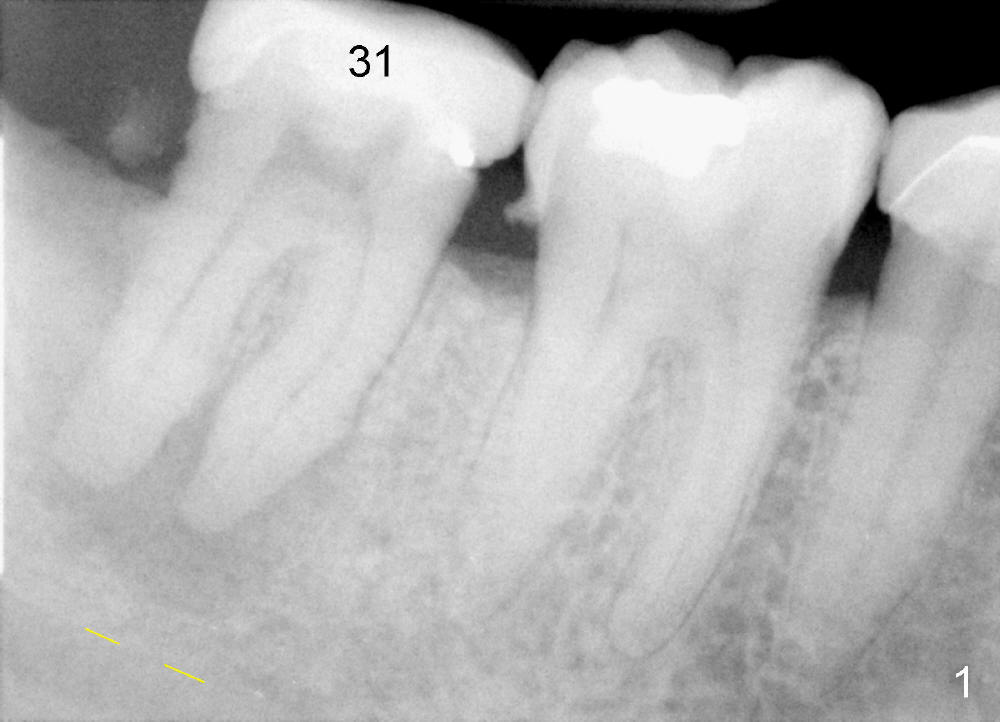

The tooth #31 of a 38-year-old lady has endo perio disease (Fig.1). Due to the large periapical lesion, there will be no solid (new) bone available for primary stability of an immediate implant (Fig.2: 7x17 mm). Yellow dashed line represents the upper border of the Inferior Alveolar Canal (IAC). Infiltration anesthesia is administered first. The mesiodistal widths of the root of the extracted tooth are 10 and 7 mm at the coronal and apical ends, respectively; the buccolingual ones 7 and 5 mm; the length 17 mm (Fig.3). The socket appears much larger than the root (Fig.4). To prevent paresthesia, no drills are used. Instead, a series of tap drills (6,7,8x17 mm) are sequentially inserted into the socket. The largest tap (Fig.5 T; 8x17 mm) binds to the socket securely with separation from IAC. Block anesthesia has to be administered before removal of the tap. A tapered implant (8x17 mm) is placed with insertion torque greater than 60 Ncm (Fig.6 I); allograft mixed with Osteogen is placed around the implant (*). Collagen dressing covers the opening of the remaining socket. The wound is protected with perio dressing, which is partially secured by an abutment (A in Fig.6). No paresthesia is reported by the patient a few hours postop.